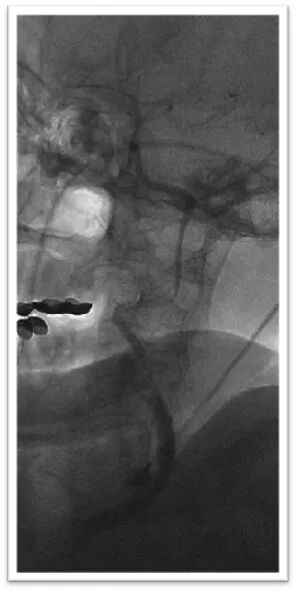

Synchro2微导丝引导微导管通过闭塞段后造影位于血管真腔,交换长导丝Synchro 300mm,顺利置入保护伞Spider 4mm于岩骨段,微导管释放6-30mm支架后造影显示支架完全覆盖血栓,正向血流未完全恢复,停留5分钟后在支架锚定下前推长鞘,使用抽拉结合取栓术取出大量血栓;